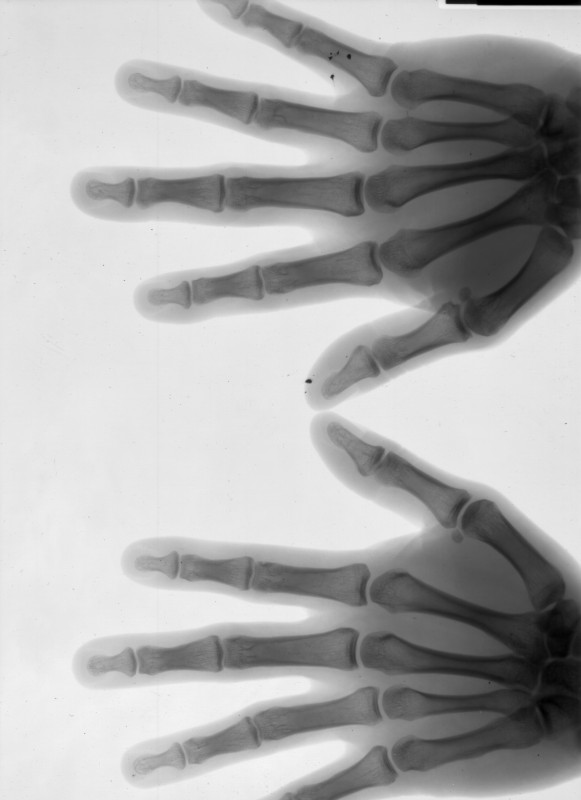

Taken at 75KV 40mAS, posterioanterior view